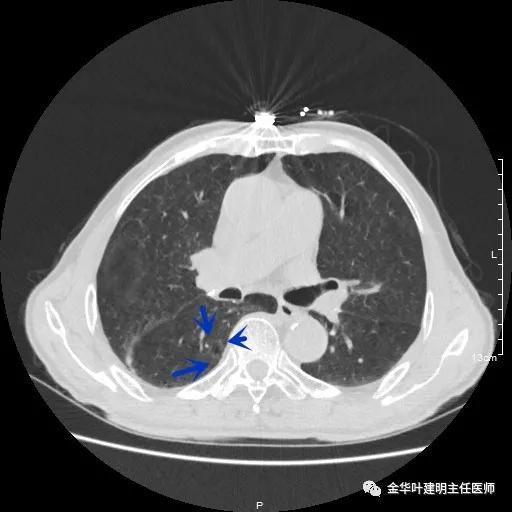

以上示右肺中叶病灶3。是混合磨玻璃结节,位置差,邻近肺门部,无法局部楔形切除,抗炎治疗后靶扫描显示了更清楚的细节,是典型的肺癌影像特征(此处未另提供)。从单病灶来看,需要行右肺中叶切除并清扫淋巴结才能得以治疗。

以上示右中叶病灶4。也是囊腔型病灶,病灶大,囊壁是磨玻璃密度,亦是较为典型的囊腔型肺癌影像。单病灶看,需中叶切除来治疗,因病灶3的存在,中叶切除可同时解决病灶3与病灶4。

以上示右下叶病灶5。也是主病灶,是实性块状分叶的占位性病变,基本可以肯定是肺癌。单病灶看需下叶切除并清扫淋巴结。

以上示右下叶病灶6。同样是囊腔型病灶,但较前几个范围小,可囊壁同样为磨玻璃影,也是较为典型的囊腔型肺癌表现,单灶来看可下叶背段切除。